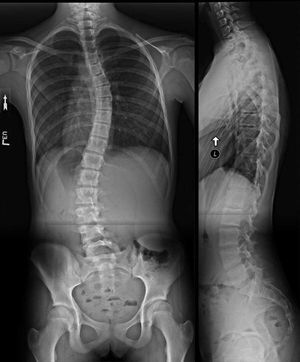

It s scoliosis, sideways curvature of spine.... Most of the cases are mild with few symptoms but some children develop spine deformities which is painful and more severe and disabling as disease progresses

We have scoliosis and because the scan is posted backwards (it says Left where it should be Right) i almost said Situs Inversus🤔.